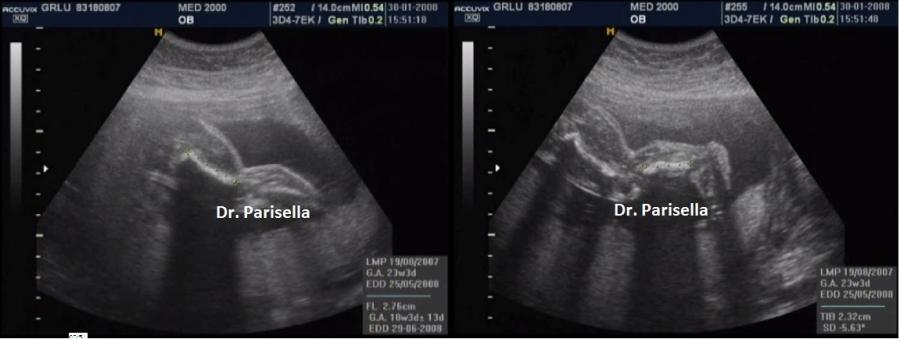

I segni principali sono la micromelia marcata, l'idrope fetale e ossificazioni ectopiche.

1. micromelia severa